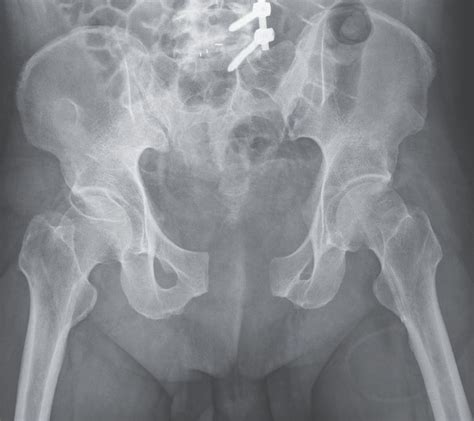

Surgical Treatment

Surgical treatment is often necessary for broken pelvis open book fractures to stabilize the pelvic ring and promote healing. Surgical options may include:

• Open reduction and internal fixation (ORIF): This procedure involves surgically realigning the fractured bones and securing them with plates, screws, or rods.

• External fixation: In this procedure, a metal frame is attached to the pelvis using pins inserted through the skin. The frame helps stabilize the pelvic ring and allows for weight-bearing.

• Pelvic C-clamp: This device is used to compress and stabilize the pelvic ring, particularly in cases of severe instability.

In some cases, a combination of surgical techniques may be used to achieve optimal stability and healing.